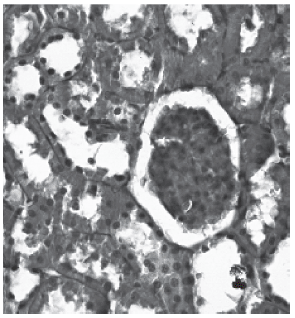

Histological examination of the kidneys from animals in the control group revealed, as expected, entirely normal histological features, as illustrated in figure 1. However, there was tubular necrosis in kidneys from animals in the amikacin treated group, initially in group 2 and particularly in group 4, as illustrated in figures 2 and 3, respectively.

Fig. 2 - Control Groups (PAS).

Fig. 3 - Group 2 (PAS).

The lumen of the tubules was filled with degenerate and desquamated epithelial desquamated epithelial cells. Furthermore interruptions in the basal membrane are present.

Fig. 4 - Group 4 (PAS).